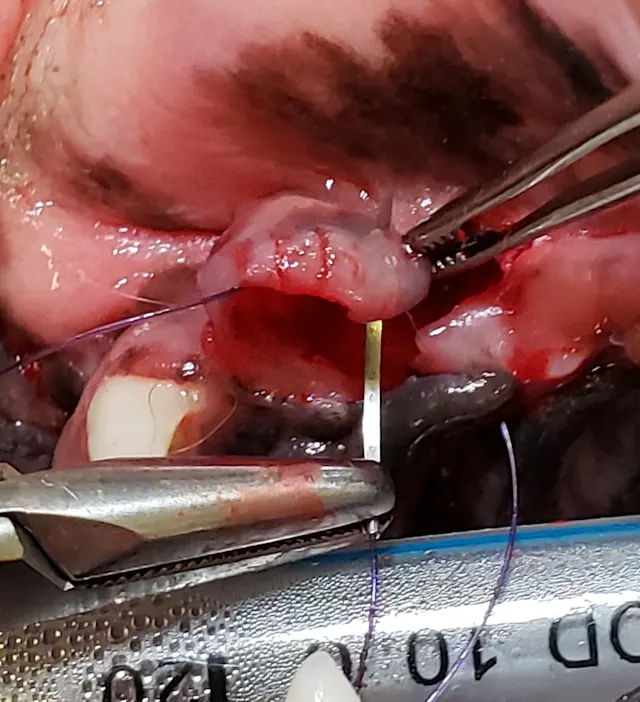

Step 11: Suture the Extraction Site

Confirm the flap is released enough to be placed over the extraction site without tension (A). If not done previously, incise a thin layer of periosteum on the underside of the flap (see Step 4). Close the mucogingival flap over the extraction site using absorbable suture (B). Use simple interrupted sutures to anchor the flap to the mesial and distal aspects and simple interrupted, cruciate, or continuous sutures to close the remaining edges (C; lines indicate where additional sutures should be placed).

A

Author Insight

Osteopromotive/conductive substance may be placed prior to flap closure but is not frequently used at this site.

A reverse cutting needle with 4-0 suture can be used to close extraction sites in dogs, and a tapered or cutting tapered needle with 5-0 suture can be used in cats. The author prefers absorbable, dyed poliglecaprone suture.